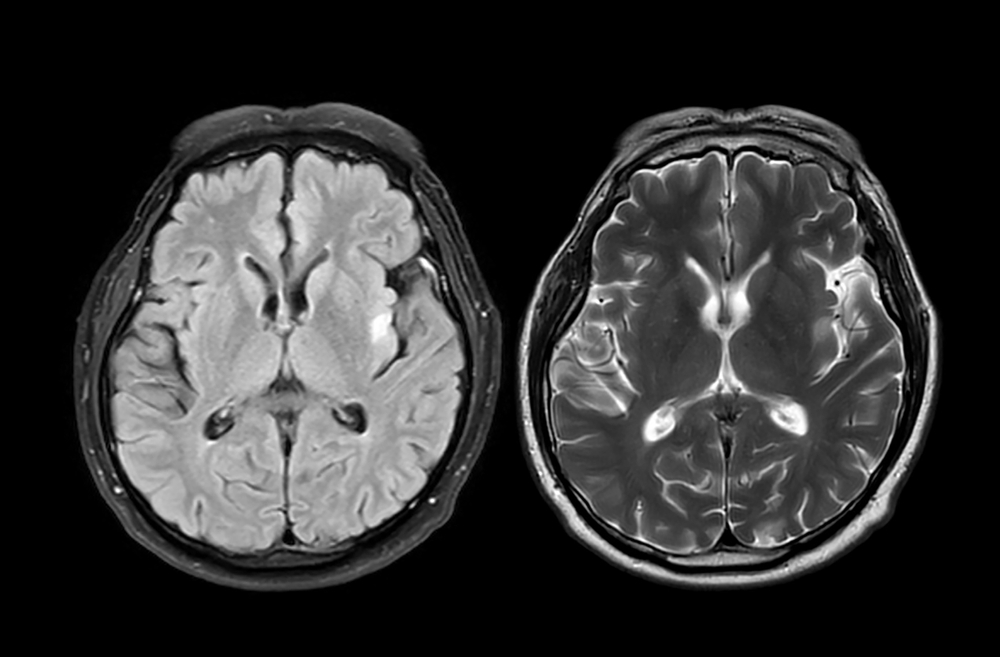

- Smegenų magnetinio rezonanso tomografija (MRT) padeda įvertinti mielino netekimo židinius, būdingus MLD.